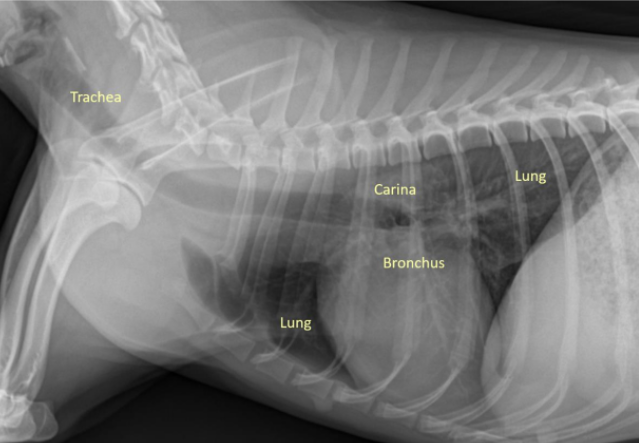

| Airways |

| ์ ์์ ์ธ ๊ณต๊ธฐ์ ํ๋ฆ : Trachea - Bronchus - Bronchioles - Lung |